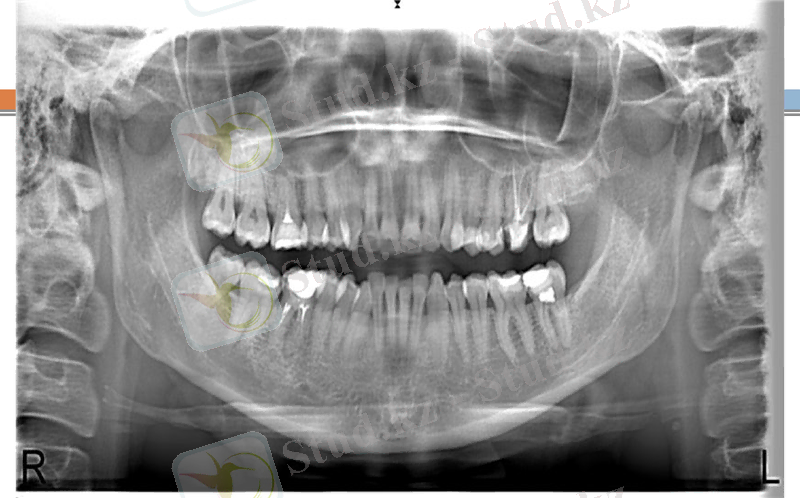

Рентгендік суретте:Альвеола өсіндісінің парадонт қабынуы бар аймағында тістер аралық қалқан сүйектер ұштарын жауып тұрған тығыз сүйек қабатының ошақты сорылуы нәтижесінде бүтіндігі бұзылғаны немесе толығымен сорылып, кемік сүйек кеуектене бастағанын анықталады. Сүйек тіні сорылып, сүйек биіктігі біраз 1/3 биіктігіне төмендеуі нәтижесінде алдыңғы тістер аралық қалқандар пішіні кертілген конусқа ұқсап қалады, кемік сүйекте ошақты немесе жайыла кеуектену үрдісі орын алады. Компактты пластинканың деструкциясы. Тістердің мойын бөлігінде периодонт саңылаулары кеңейгені байқалады.

Тістердің қозғалғыштығы 1-2 дәрежеде

Рентгендік суретте: Тістер аралық қалқан сүйектер түбір ұзындығының 1/3-1/2 бөлігіне дейін біркелкі емес көлденең сорылған, сақталған бөліктеріндегі кемік сүйекте жайыла кеуектену үрдісі орын алған. Периодонт саңылауы кеңейіп, сүйек қалталары пайда болған.